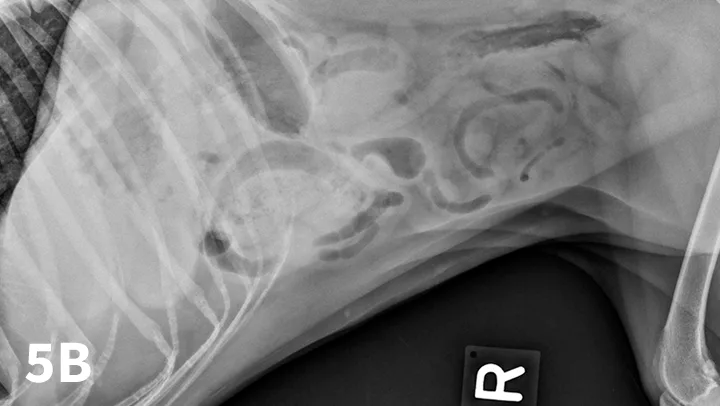

A ventrodorsal abdominal radiograph showing a round metallic object in the small intestine.

Radiographic features of small intestinal mechanical obstruction depend on its completeness, location, and duration.2 Whereas metallic FBs or those with mineral content are easily recognized within the GI lumen (Figure 1), nonmineralized, nonmetallic objects (eg, cloth) within the GI tract are more difficult to identify (Figure 2). Some may be recognized by their geometric shape. The most consistent sign of mechanical obstruction is variable dilation of intestinal loops proximal (orad) to the obstruction (described as a mixed population of small intestine; Figure 2). Determination of small intestinal diameter can be made by comparing it to the L5 vertebral body height in dogs.3 Values greater than 1.6 are suggestive of obstruction (Figure 2A). In cats, a ratio of the maximum small intestinal diameter to vertebral end plate height of L2 greater than 4 indicates a high likelihood of intestinal obstruction.4

FIGURE 1

VD abdominal radiograph of a 1-year-old cat with a 2-day history of vomiting and a nonobstructing metallic foreign body. A coin with a radiolucent center caused by erosion is present within the small intestinal loops in the right midabdomen. No dilated loops of small intestine are seen to indicate mechanical obstruction.